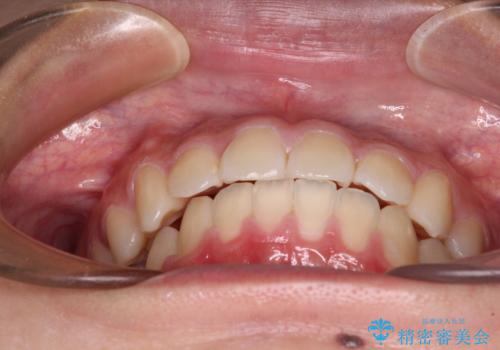

- 下顎の前突感と前歯の叢生を気にして来院された患者様です。

下顎前方位の骨格のため、下顎歯列に対して上顎歯列の幅が狭くなっていました。

急速拡大装置を用いて上顎骨を側方に拡大し、上顎の叢生を解消するとともに下顎歯列拡大により下顎の叢生も解消することとしました。